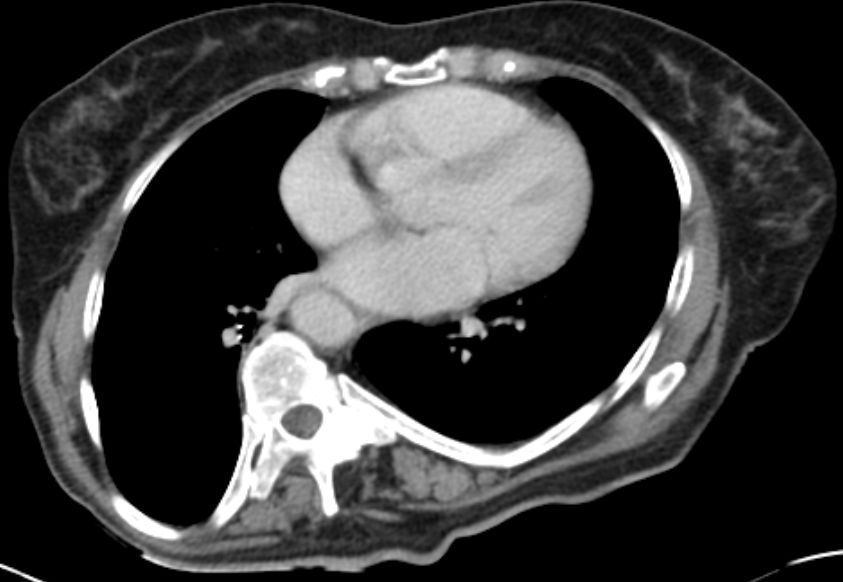

| Fall | 72-jährige Frau mit einem Beckentumor.![]()  |

![]()  |